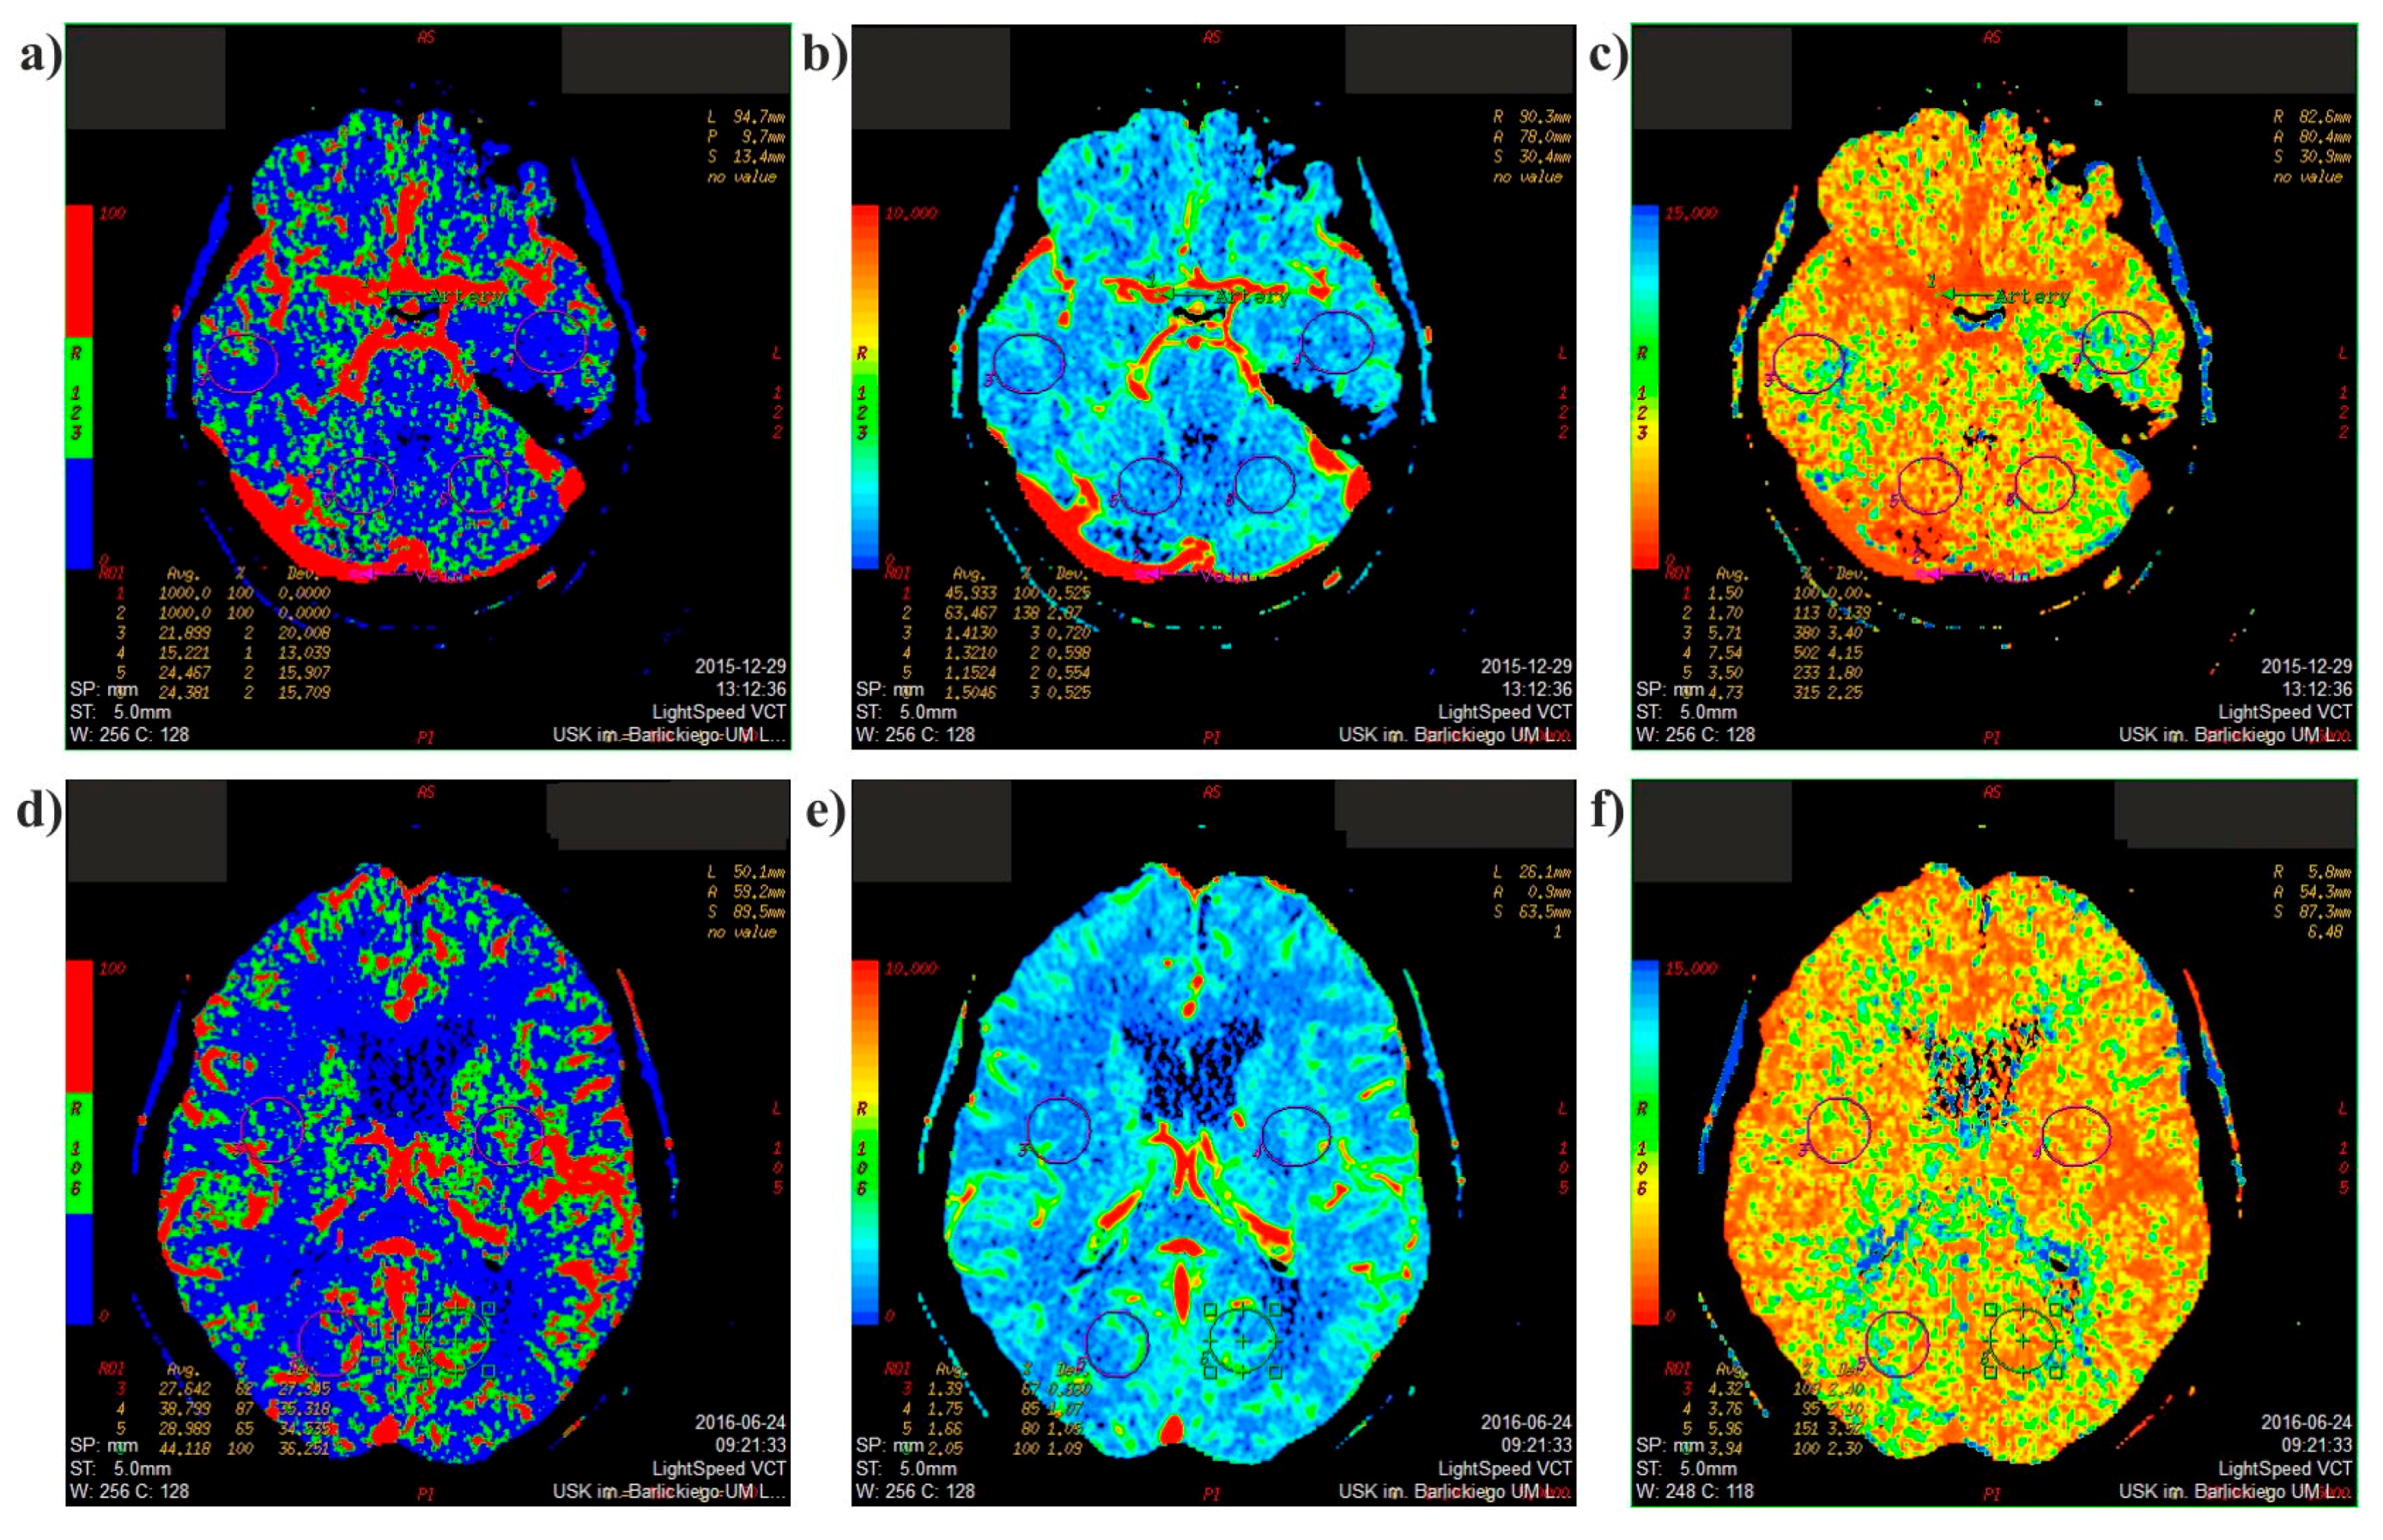

2.1. Medical Data